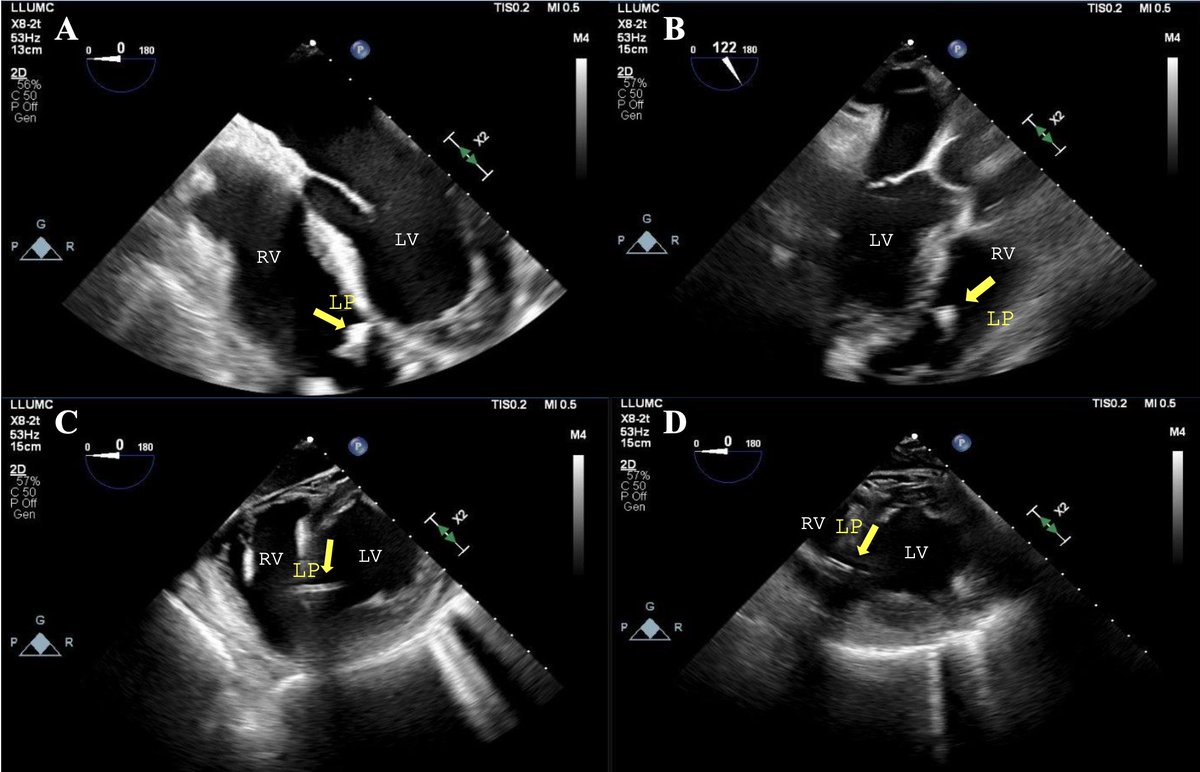

**Study 3: Step-by-step approach to ultrasound-guided leadless pacemaker implantation @DJ_Lakkireddy @MohitTuragam @jkewcharoen et al share a practical, image-guided protocol using TTE, ICE, or TEE to optimize LP placement and reduce contrast/radiation exposure. *Echo confirms